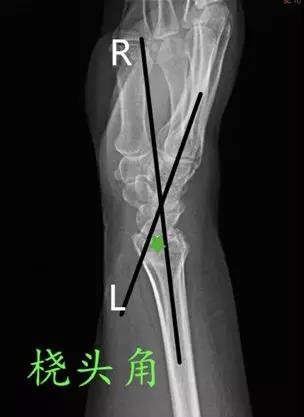

- 桡头角:腕部侧位片上桡骨和头状骨中轴线的夹角。

- 正常值:6°~26°

- 临床意义:>26°提示腕关节不稳。

- 桡月角:在腕部侧位片上桡骨和月骨(近端与远端)中轴线的夹角。

- 正常值:0°~15°

- 临床意义:屈曲>15°提示掌曲不稳,背伸>10°提示背伸不稳。

- 头月角:腕部侧位片上头状骨和月骨中轴线的夹角。

- 临床意义:>20°提示腕关节不稳。

- 舟月角:在腕关节侧位片舟骨与月骨(近端与远端)中轴线的夹角。

- 正常值:30°~60°

- 临床意义:舟月角>70°提示腕背伸不稳,<30°提示腕掌屈曲不稳;>60°或移位>1mm,需要对舟骨进行切开复位内固定;舟月间距<3mm,间距>3mm提示舟月韧带撕裂。